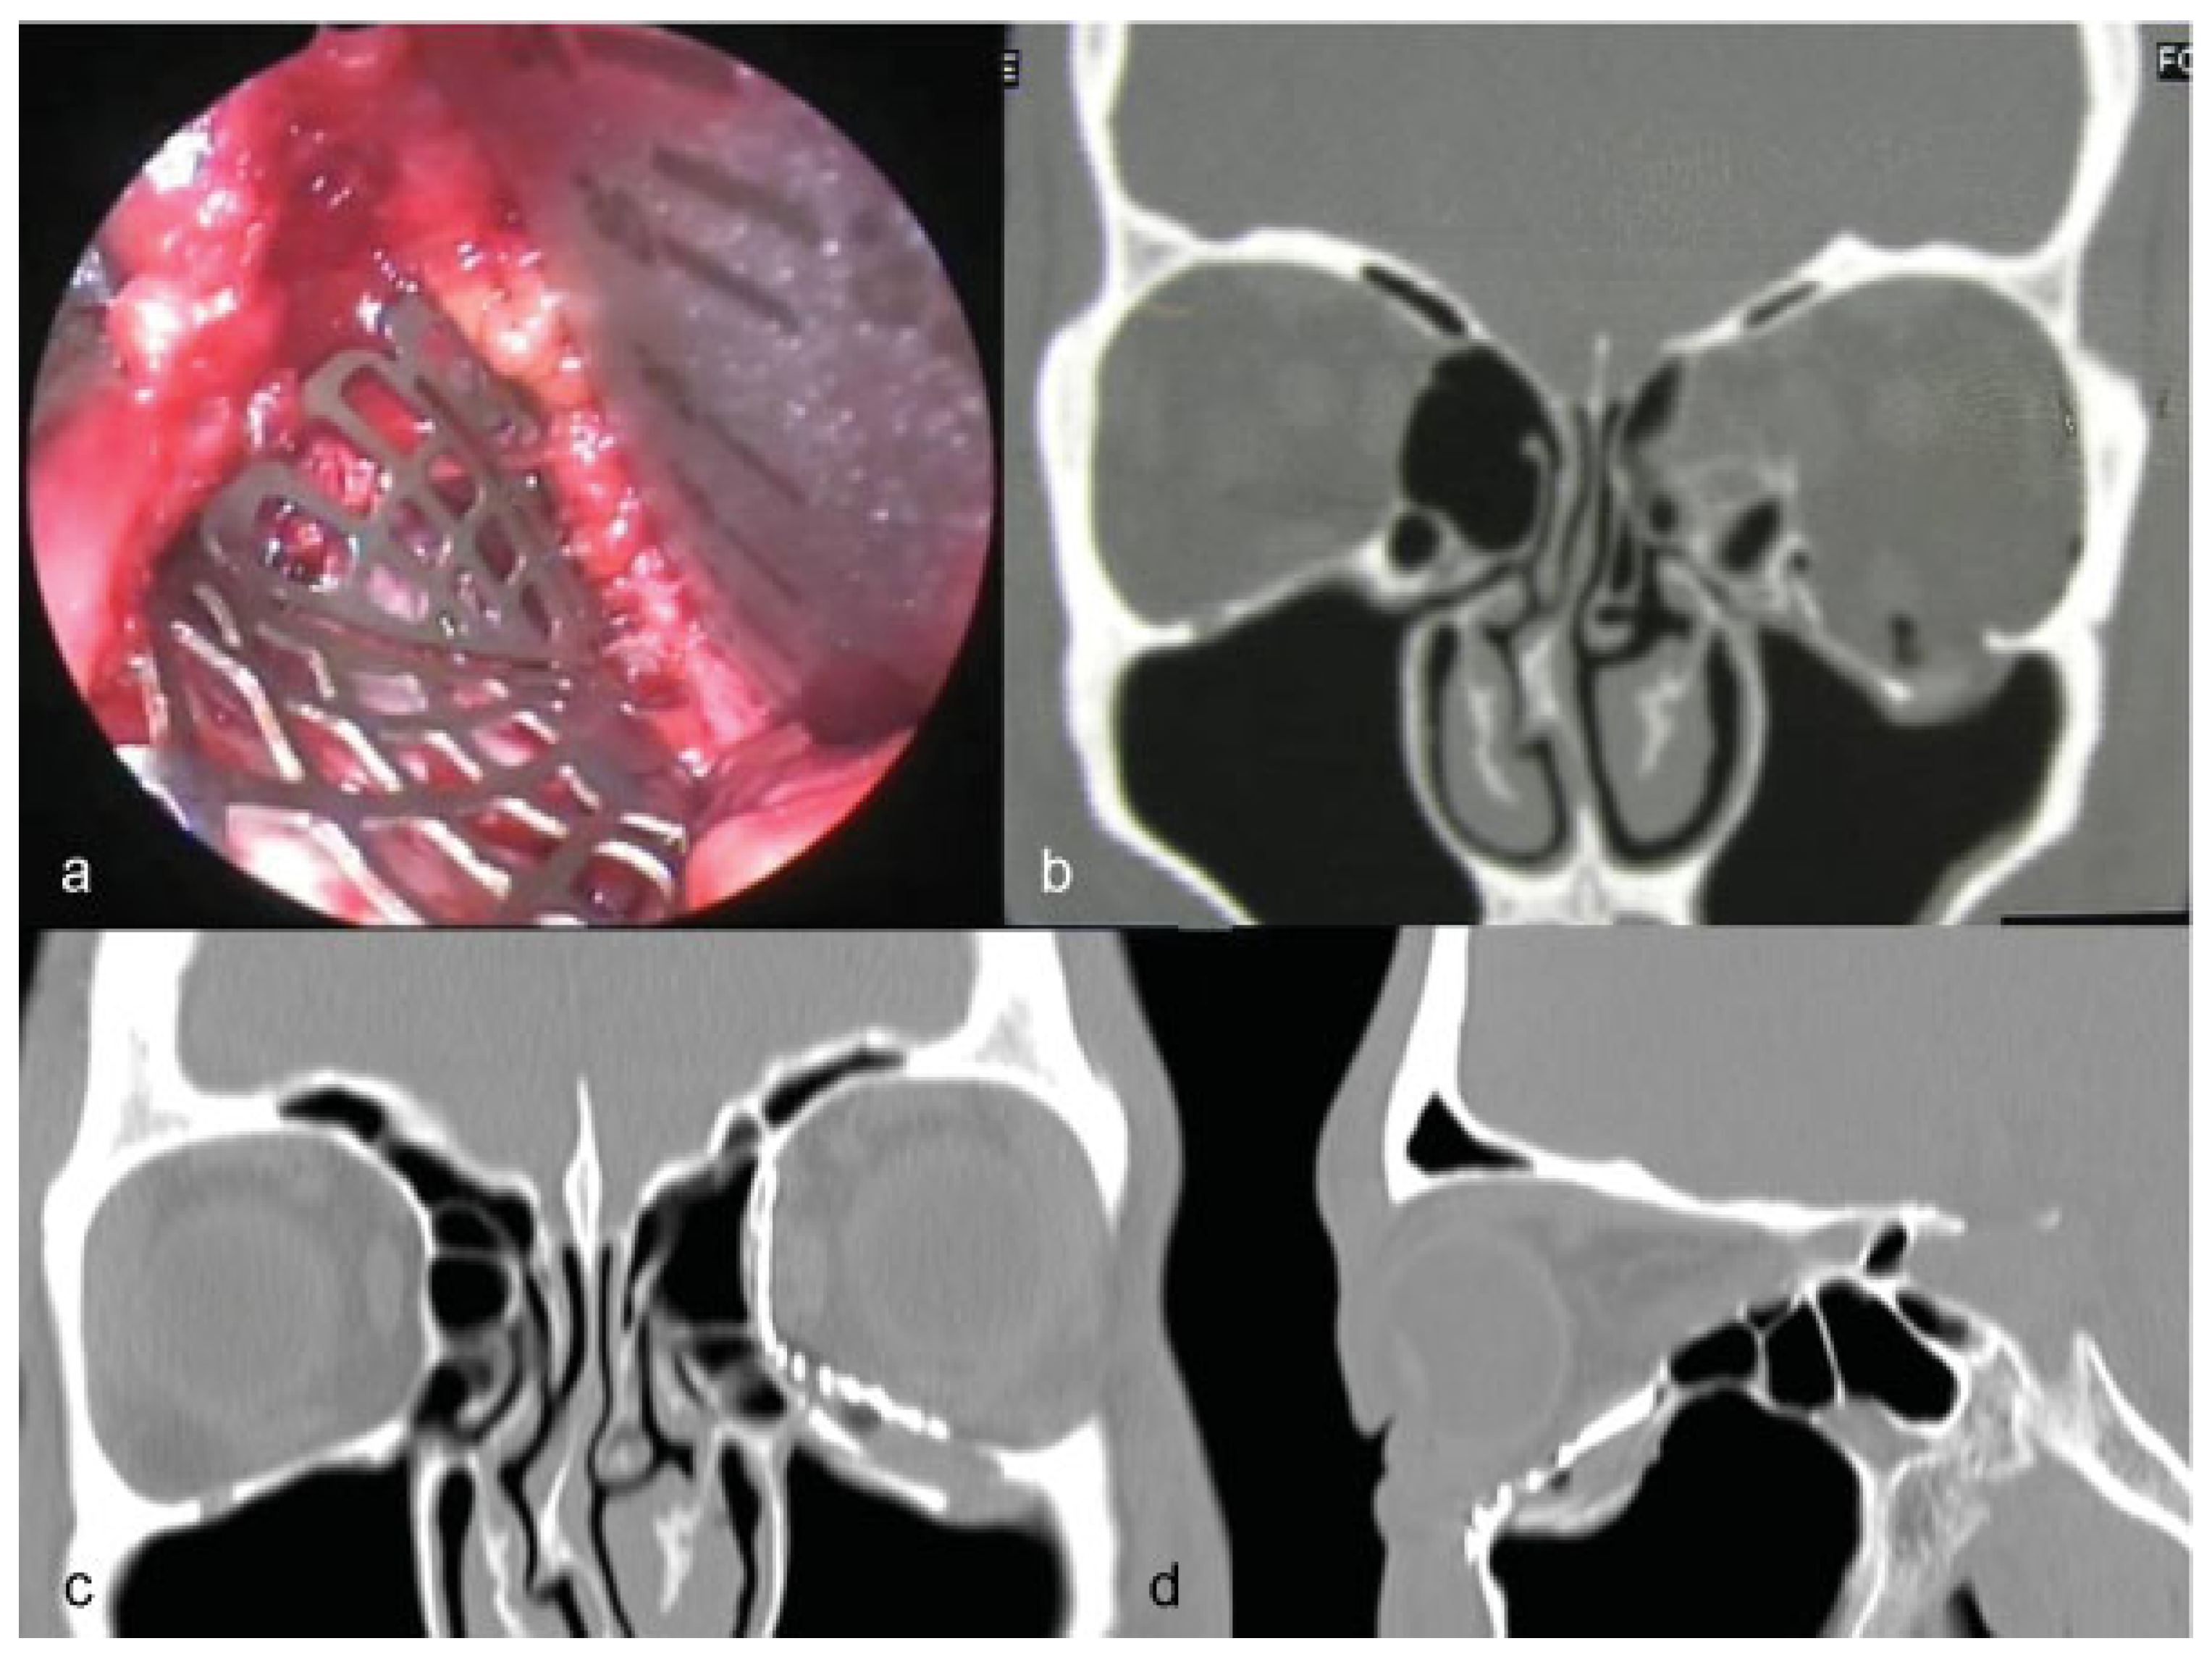

Figure 4. Group 2 (ENDO). Endoscope-assisted seating of a radial orbital mesh in isolated medial wall fracture. (a) The mesh is not properly seated and the inferior margin of the fracture is not reached. (b) Correct anatomical seating with good relationships between the mesh limit and the fracture ledges. (c,d) Post–CT scan axial and coronal view. In this case the quality of orbital reconstruction was rated as satisfactory.